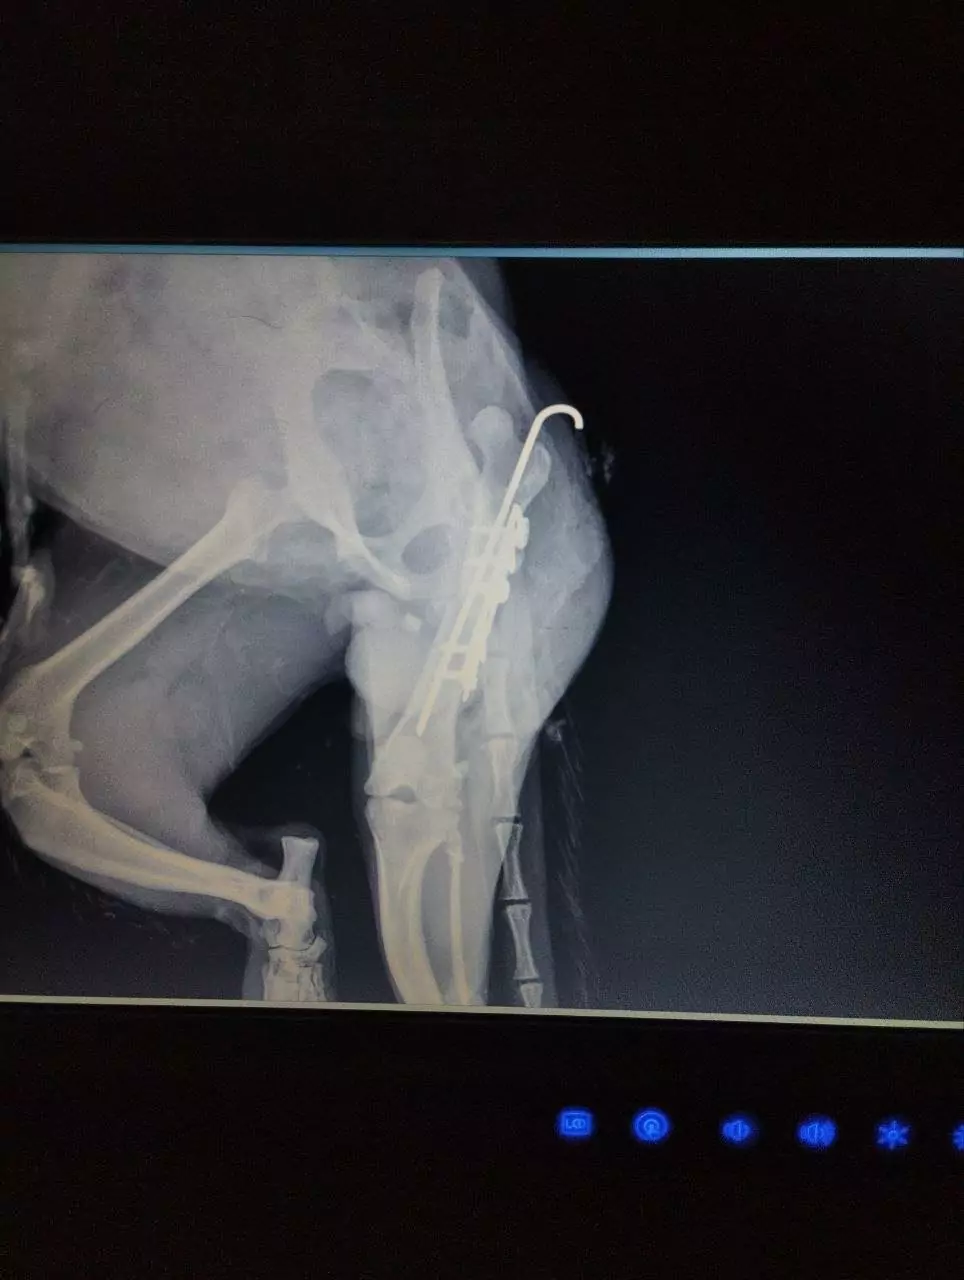

За їхніми даними, дворічного кота на ім’я Серьожка доставили до Харкова військові. Під час огляду у нього виявили відкритий перелом правого стегна, а також рвані рани тазових кінцівок.

Лікарі провели складну операцію — остеосинтез стегна — та призначили інтенсивну терапію. Після втручання тварина поступово почала відновлюватися.